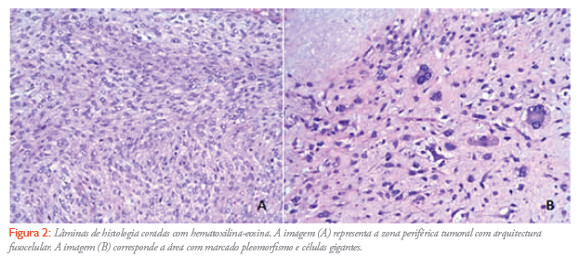

Mulher de 58 anos, caucasiana, viúva, natural e residente em santarém, com antecedentes de HTA, diabetes mellitus tipo II, AVC isquémico sequelar e anemia microcítica. Recorre ao serviço de Urgência do hospital distrital de santarém (HDS), por epigastralgias e astenia com 4 meses de evolução e agravamento da frequência e intensidade na última semana, perda de peso de aproximadamente 15 kg nos últimos dois meses e saciedade precoce. Ao exame objectivo apresentava-se vigil, desorientada no tempo, pouco colaborante, idade aparente superior à real, corada, hidratada, emagrecida. À inspecção abdominal detectou-se proeminência na região epigástrica, palpando-se massa de consistência dura, não dolorosa, que se estendia até 7 cm abaixo da apófise xifoideia. De referir ainda ligeira diminuição da força muscular à direita, sequela do AVC. A doente ficou internada no serviço de medicina por epigastralgias de etiologia a esclarecer. Realizou-se TAC Toraco-Abdomino-pélvica que revelou volumosa massa tumoral atingindo o epigastro, o hipocôdrio e o flanco esquerdos mede aproximadamente 20 cm de maior eixo no plano axial, tem limites relativamente nítidos não se observam adenopatias . A nível hepático não se evidenciam lesões focais (Figura 1). O caso clínico foi discutido em consulta multidisciplinar de decisão terapêutica onde foi considerada a indicação para ressecção cirúrgica urgente. A doente foi submetida a tumorectomia, pancreatectomia caudal e esplenectomia por aderência da massa tumoral ao baço e pâncreas. Tanto o procedimento cirúrgico como o pós-operatório decorreu sem intercorrências com alta médica no 12º dia após a intervenção. O resultado anatomo-patológico foi: peça de tumorectomia que pesa 3800g e mede 25x25x15cm. Macroscópicamente o tumor estava quase totalmente coberto por peritoneu, e a superfície de secção era acinzentada, sólida e mole, tendo uma área de necrose central que ocupa 60% da massa tumoral.Microscópicamente o tumor mostrava focalmente padrão fusocelular e estoriforme, predominando, no entanto, as áreas desorganizadas constituídas por células marcadamente pleomórficas (Figura 2). Imunohistoquimicamente identificou-se positividade intensa com Vimentina, e focal e escassa com Actina de músculo liso e CD34, sendo o CD117 (C-Kit) e os restante marcadores de diferenciação epitelial, miogénica, lipogénica e neural negativos. Isolam-se 8 gânglios com diâmetros entre 0,1 cm e 0,7 cm. Conclusão: sarcoma pleomórfico indiferenciado de alto grau (histiocitoma fibroso maligno). Gânglios linfáticos sem metástases. O tumor rasa a margem cirúrgica. Baço e pâncreas aderentes ao peritoneu, sem infiltração tumoral. Na reavaliação em consulta multidisciplinar, foi considerado não haver indicação para tratamento adjuvante com quimio ou radioterapia, apesar do elevado potencial de recaída da lesão, ficando a doente em vigilância na consulta de Cirurgia do HDS.